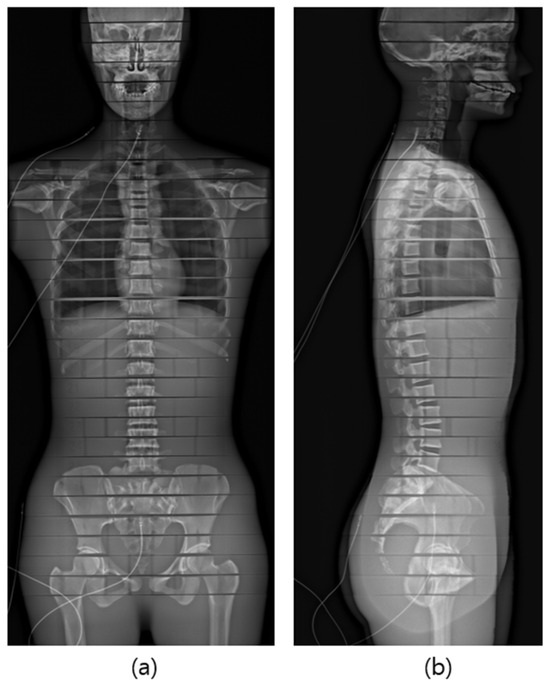

The phantom was meticulously positioned at the center of the equipment in the posteroanterior (PA) orientation, aligning the anterior–posterior surface of the phantom with the equipment’s guidance lines. The X-ray scanning range encompassed the entire region, extending from the height that included frontal sinuses to the proximal femur (Figure 2 and Figure 3).

Figure 3. Radiograph of phantom from EOS examination. (a) PA posture, (b) Lateral posture.